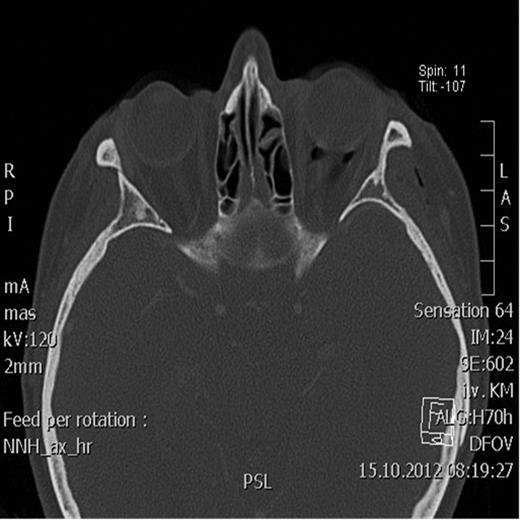

Spiral computed tomography (CT) was performed using 1 mm slices with a soft tissue and bone algorithm. A non-dislocated orbital floor fracture and a large amount of intraorbital emphysema were found, especially retrobulbar between the ocular muscles and around the optic nerve, causing exophthalmos (the distance from the corneal apex to the line connecting orbital rims was 18.8 mm; normal 9.0 mm) (Figs 1–2).

Axial CT scan showing massive emphysema of the orbit leading to proptosis.